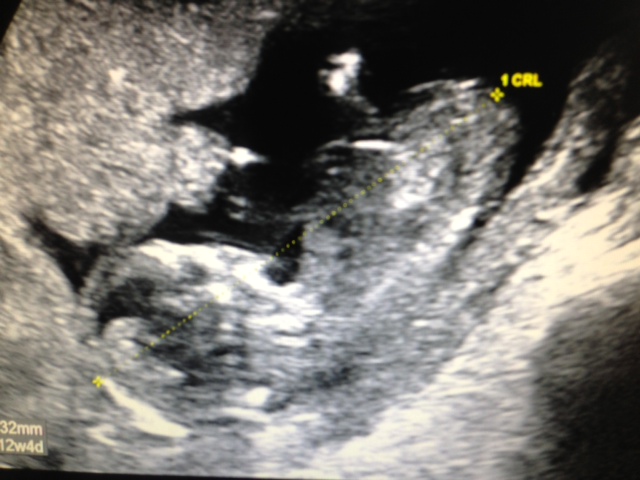

These are my pics from my scan at 12+3. I'm not really sure if you can see anything but I would love to hear your opinions.

Attachment 11722Attachment 11723Attachment 11724

Sorry I can't make out a clear enough nub to make a guess...but congrats on baby :)